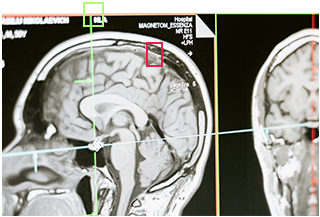

Building AI solutions for every healthcare need

Powered by Federated Learning

Trains robust models on distributed data across different hospitals without exposing their patients’ sensitive data.

Interpretable by design

Unique algorithms allow researchers to understand the model’s conclusions and identify biomarkers.